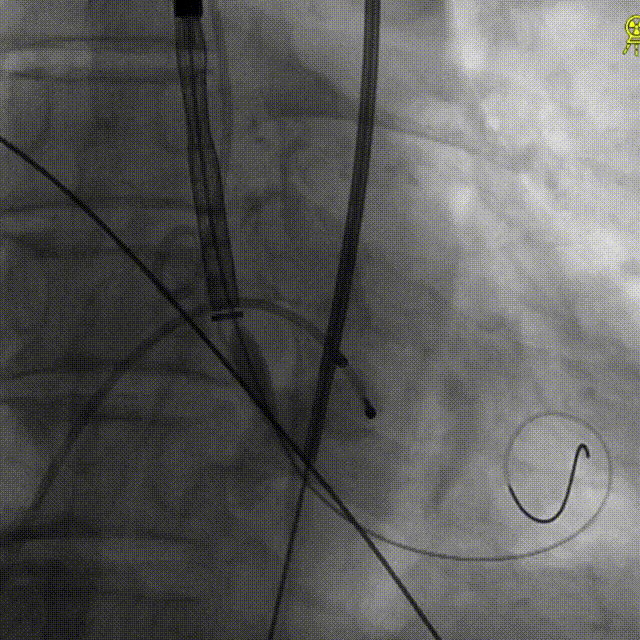

TaurusOne® 输送器顺畅过弓

造影辅助定位

精准释放